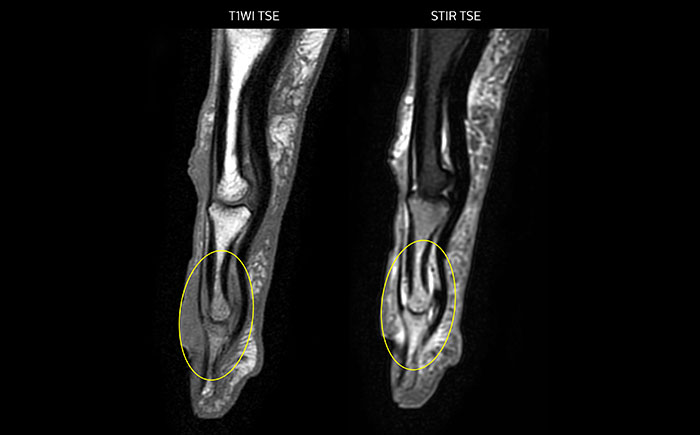

MRI of the finger

MRI of the finger with high SNR and good resolution in a 10 cm field of view on Prodiva 1.5T. The diagnosis in this 63-year-old patient is bone elasmanosis.